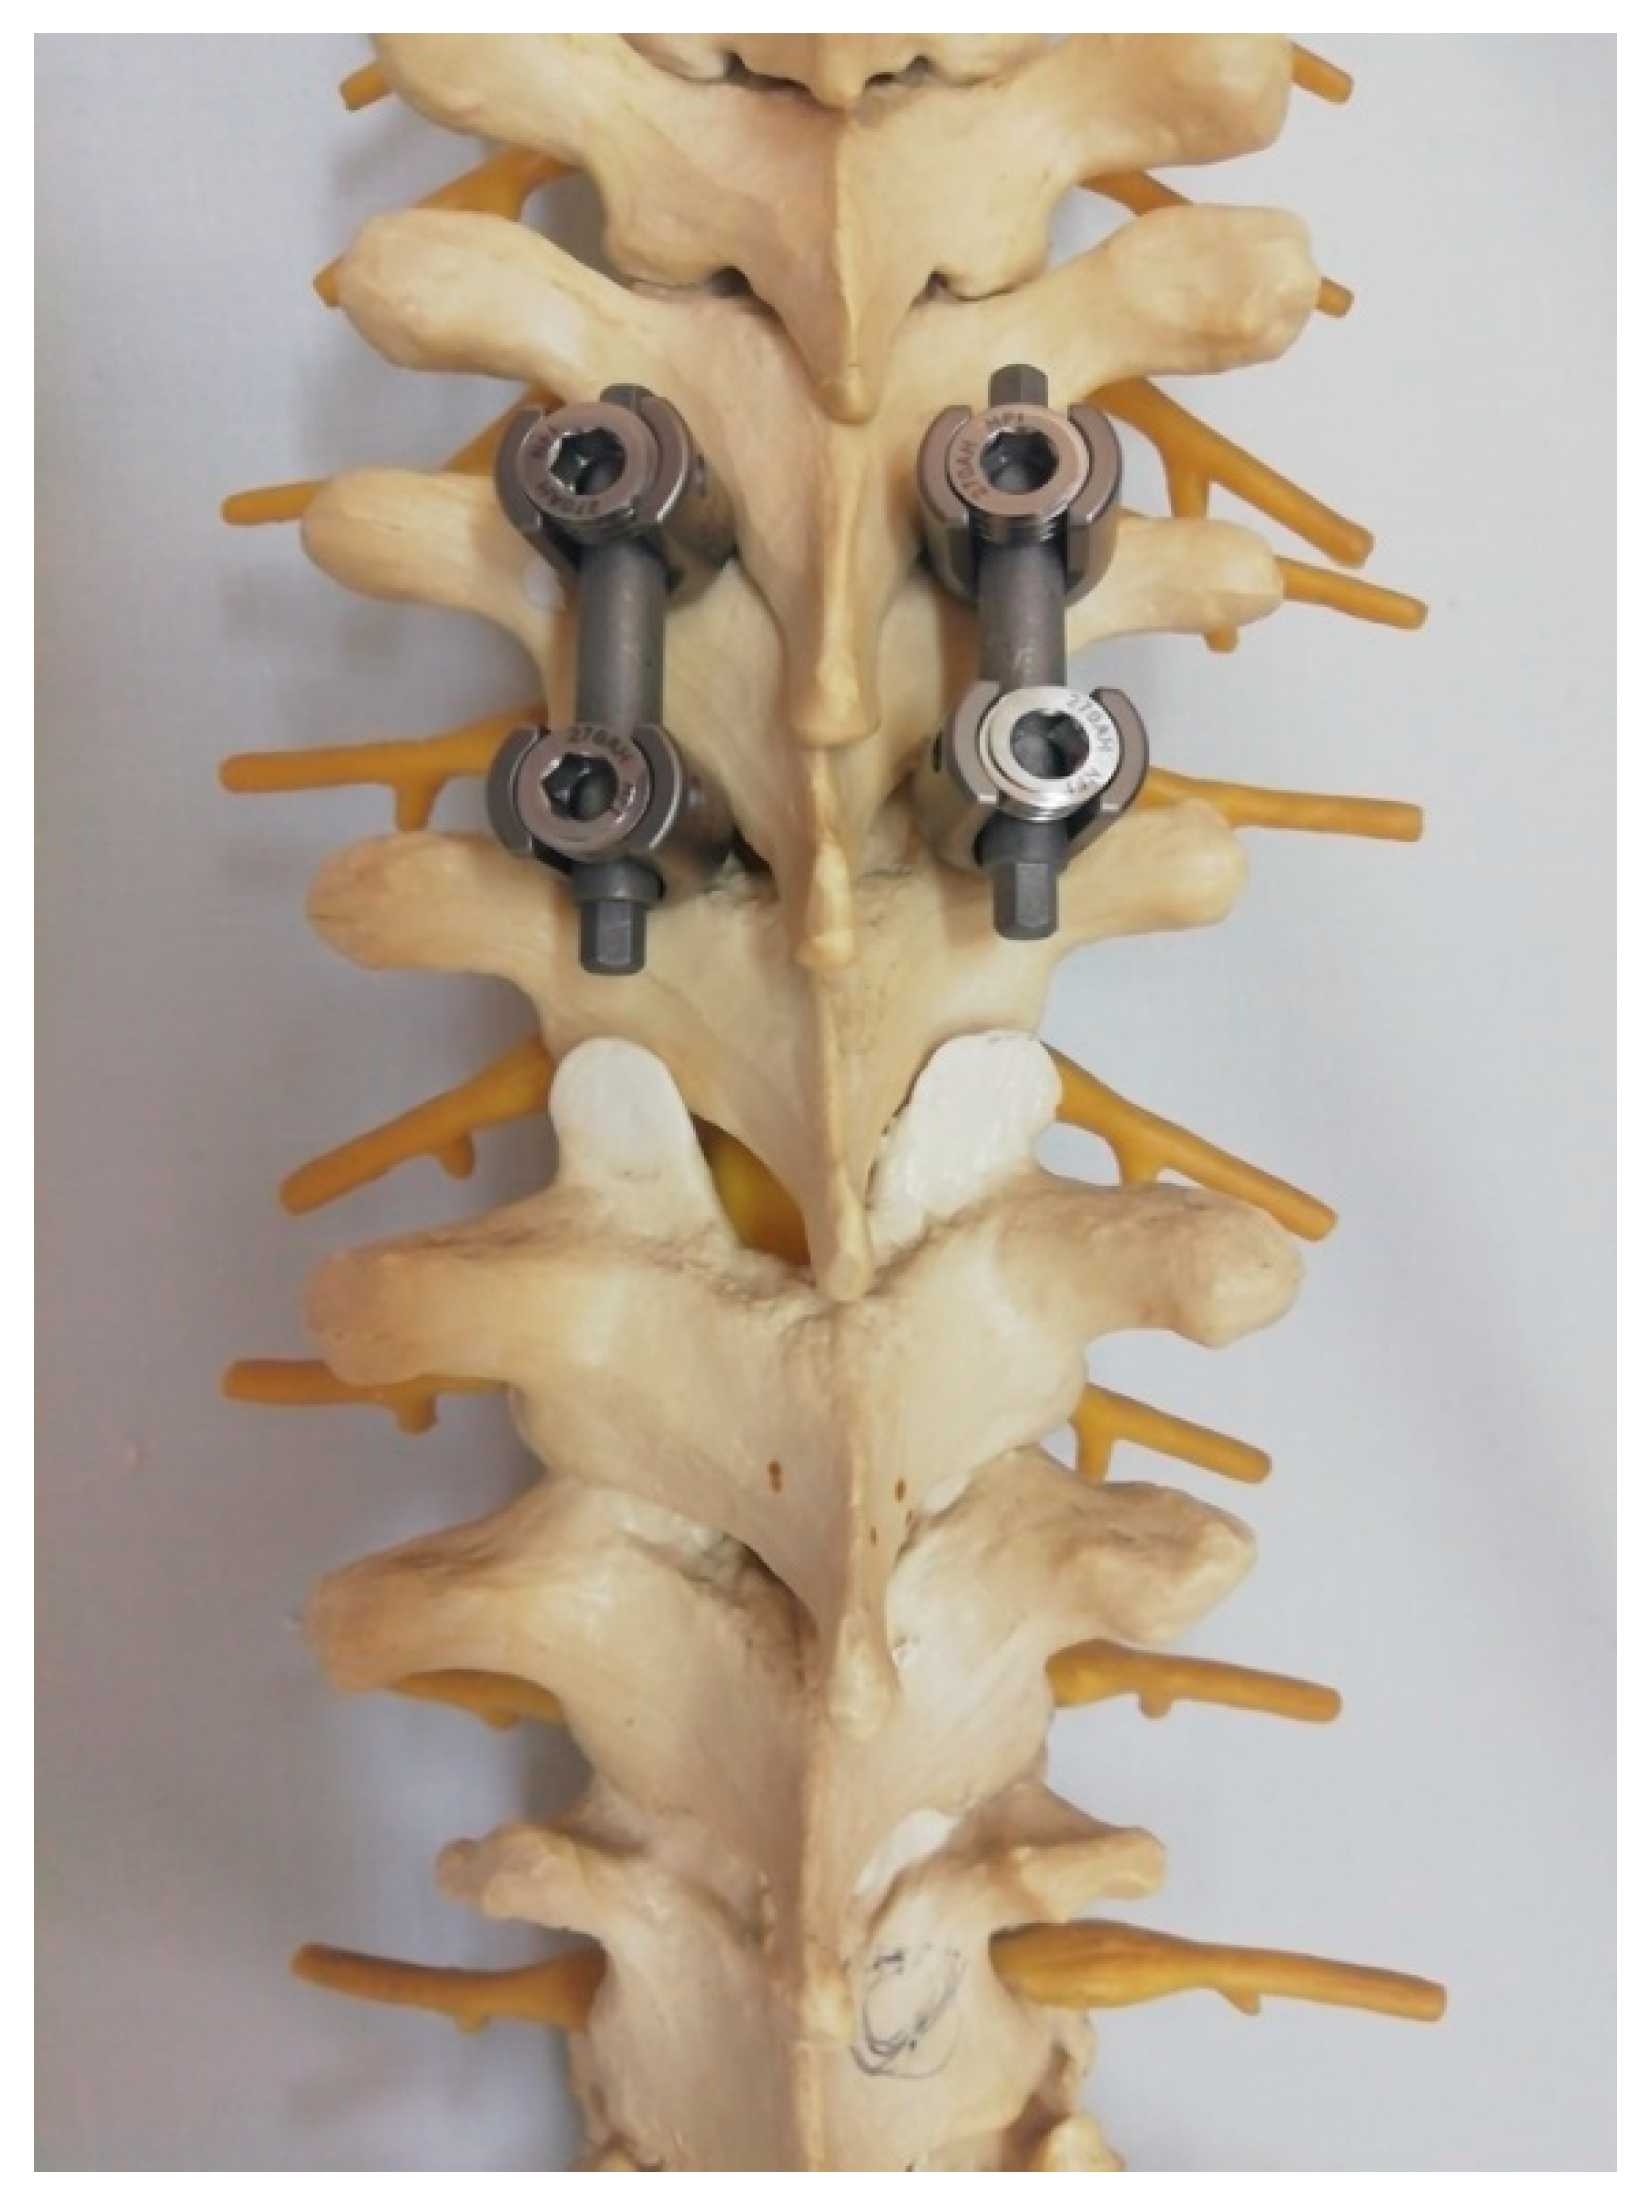

Figure 1.

A bilateral dislocation of the facet joint of the lower thoracic spine displayed on a plastic model. Arrows highlight the bilateral discloation of the facet joint.